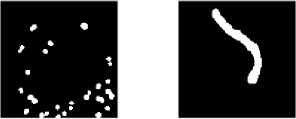

After the contrast stretching process, the segmentation process is carried out based on the threshold value with the equation (4). Because this study used hue images and saturation images, the threshold value used has a range of 0.4 to 0.7. It depends on the results of the contrast stretching the image, whether it is dark or light. The thresholding process results are a binary image, an image with two values, namely 0 (black) and 1 (white), as shown in Figure 8.

Figure 7. Thresholding image of (a) Staphylococcus aureus, (b) Streptococcus pneumoniae, (c) Corynebacterium diphtheriae, (d) Neisseria gonorrhoeae and (e) Mycobacterium tuberculosis

Figure 7 shows that the threshold image can represent most forms of bacteria, but there are some bacteria such as Neisseria gonorrhoeae and Mycobacterium tuberculosis that need to be resegmented. This is because there is still noise in the segmentation image based on the threshold value. Noise is meant objects that are not parts of the bacterial body, such as paint residues and other objects like Polymorphonuclear (PMN) cells. PMN itself is one of the white blood cells that will appear if there is an infection in the body. In the image of Neisseria gonorrhoeae bacteria, the shape of polymorphonuclear cells (PMN) is also segmented, so it is necessary to do segmentation based on area. To perform the segmentation, the process is continued by labeling the object and finding the area value using a chain code with the proximity of 8 neighboring pixels. This process is known as the Channel Area Thresholding (CAT) segmentation technique [19].

In this research, all bacterial images were segmented based on the Channel Area Threshold (CAT) value, but the range of the threshold values differed depending on each bacterium's area. The threshold value for the CAT segmentation technique is denoted [S.Area]. The value of the threshold area [S. Area] used varies depending on the area of each bacterium. Determination of S.Area is to use two threshold values, namely [S. Area] ≥ 5 & [S. Area] ≤ 100 was used to remove other objects such as PMN in Neisseria gonorrhoeae, while Streptococcus pneumoniae, Corynebacterium diphtheriae, and Mycobacterium tuberculosis, two threshold values were [S. Area] ≥ 50 & [S. Area] ≤ 7000. Then in Staphylococcus aureus, the difference in the upper threshold value [S. Area] ≤ 10000. The results of the CAT segmentation are shown in Figure 8.

Figure 8 shows the results of the segmentation image where there are only bacterial objects, without any noise such as staining or other cells (PMN) in the bacterial image (d) Neisseria gonorrhoeae. The following process is feature extraction based on the shape (morphology) of bacteria. Morphological features are used to classify bacteria that cause ARI because the characteristics of the shape of the bacteria are in accordance with Figure 2, so the features used are bacterial count, area, perimeter, and Shape factor. The results of bacterial feature extraction are shown in Table 2.